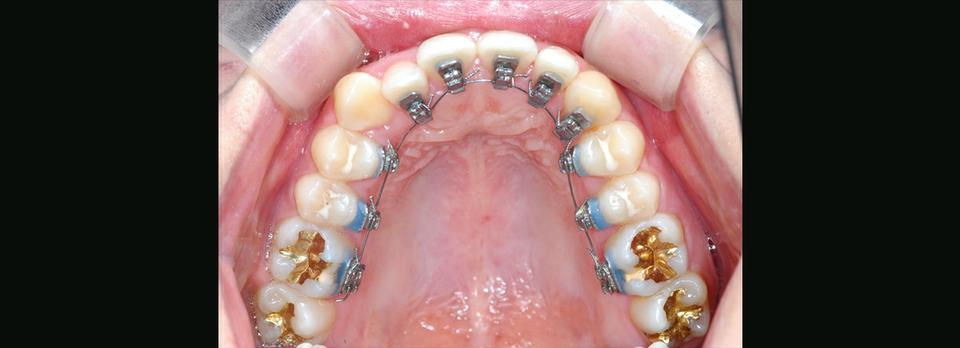

• 5. Indirect bonding

Individual transfer tray를 사용해 맞춤 제작된 안보이니 설측 브라켓은 정밀하고 효율적으로 각 치아에 부착되고, preformed straight archwire를 차례차례 교체하면서 치료는 편리하게 진행됩니다.